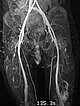

In coronal, T2-weighted, fat-suppressed MRI at 32 months of age, the characteristic strongly hyperintense (= white) signal of a slow-flow vascular malformation is found in the labial lesion. In addition, a similarly strong hyperintense signal in an intramuscular lesion is seen in the vastus lateralis muscle of the left thigh. Thus, a vascular malformation is very likely.

In the late phase of dynamic, high temporal resolution, contrast-enhanced MR angiography 135 seconds after i.v. contrast administration, there is slow, delayed contrast pooling in the lesion. Thus, an arteriovenous malformation with its rapid flow can be clearly excluded. Additional slow contrast pooling of the second lesion on the lateral distal left thigh.